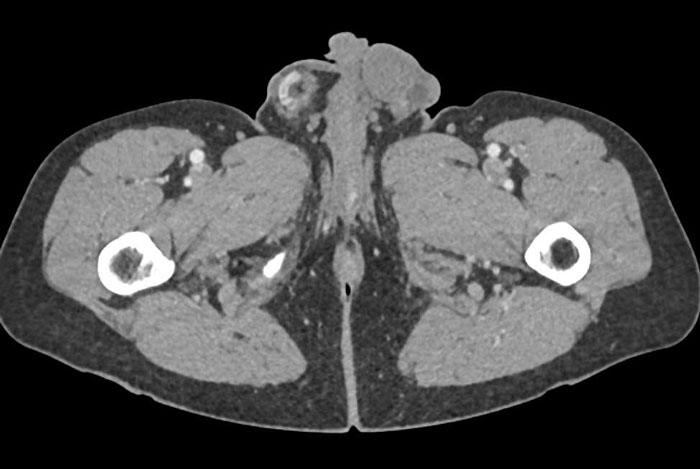

The case study says AI has great potential in the medical sphere

Image credits: Annals of Clinical Case Reports

According to the aforementioned case study, it is AI’s ability to learn and then imitate human reasoning, along with its integration into medicine, that made all these diagnoses possible.

“Artificial Intelligence now touches most areas of medicine, from the production of medical goods to diagnostics, treatment, and research in all its facets.”

“Its application holds great potential for rationalization in all areas of applied medicine and in the structural components of the entire healthcare system.”